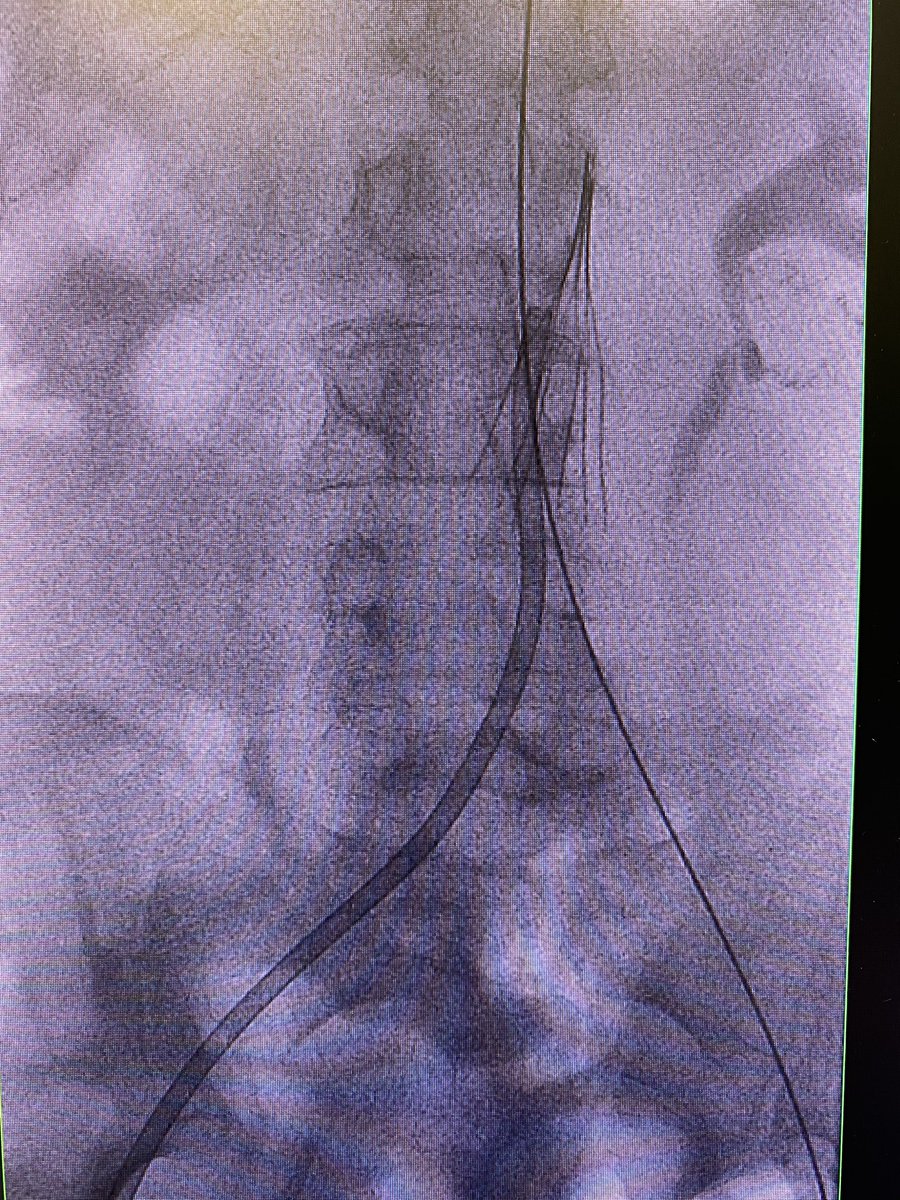

RT if you love aspiration thrombectomy! I ❤️control room fan fair 🤷‍♂️ | Iliocaval clot s/p filter placement in a trauma pt suspected due to poor preload + collapsed suprarenal IVC—used Penumbra Vascular Lightning12 #PE #MIIPs #irad #withoutascalpel Society of Interventional Radiology SIR RFS SIR ECS